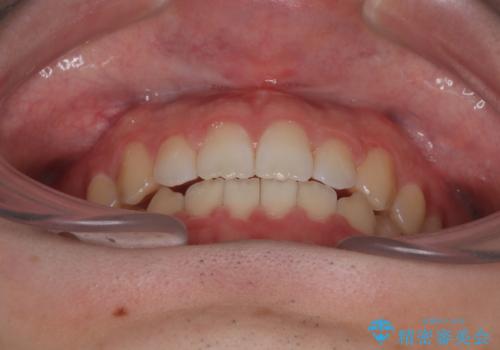

- インビザラインモデレート

- 治療期間

- 11ヶ月

マウスピース矯正特有の奥歯への圧下により、一時的に噛みにくさを感じる場面もありましたが、

装着時間の調整と経過観察を行うことで症状は改善し、スムーズに治療を完了しました。